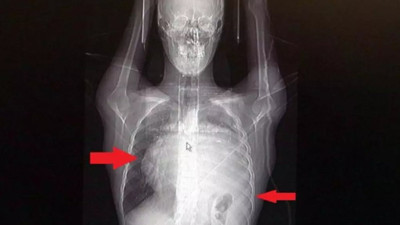

Kalbi 12 santim kaydı akciğeri kâğıt gibi ezildi. İnanılmaz ama gerçek İstanbul’da yaşayan 21 yaşındaki gencin başına inanılmaz olaylar geldi. Nefes darlığı şikayetiyle gittiği hastanede göğsünde kitle olduğunu öğrenen gencin kalbi tümörün büyümesi nedeniyle 12 santimetre kaydı. Öte yandan sol akciğeri kağıt gibi ezildi

Trabzon'da hastaneye karın ağrısı şikayetiyle gitti! Hayatının şokunu yaşadı Trabzon'da, karın ağrısı ve yürüme güçlüğü şikayetiyle hastaneye başvuran bir hastanın karnından, tümör haline gelen 26 kilogramlık kitle başarılı bir operasyonla çıkarıldı.

Dev kütleyi gören şaşkına döndü! Böyle bir kitleyi literatürde hiç göremedim Trabzon'da karın ağrısı şikayetiyle gittiği hastanede Hasan O.'nun (64) karnından 26 kiloluk tümör çıkarılan ameliyatta yer alan Genel Cerrahi Uzmanı Operatör Dr. İsmet Çelik, "Kocaman kocaman damarlarla ilintileri vardı. Ameliyat yaklaşık 1,5 saat sürdü. Böyle solid ve böbrek kaynaklı bir kitleyi literatürde hiç göremedim. Bu sadece Türkiye için değil, dünya çapında bir şey" dedi.